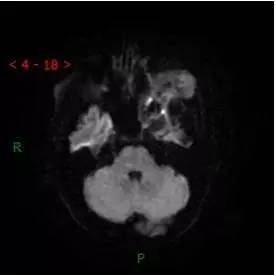

DWI

解析:本病例为中颅窝至颞下窝沟通性病变,对周围骨质主要呈膨胀压迫性改变,伴囊变、出血。

答案:C

病理:(中颅底内外沟通肿瘤) 神经鞘瘤,伴出血,局灶细胞较丰富。免疫组化结果显示:EMA(-), P53(-), S100(3 ), NF(-), PR(-), desmin(-), Ki-67( ,5-10%)